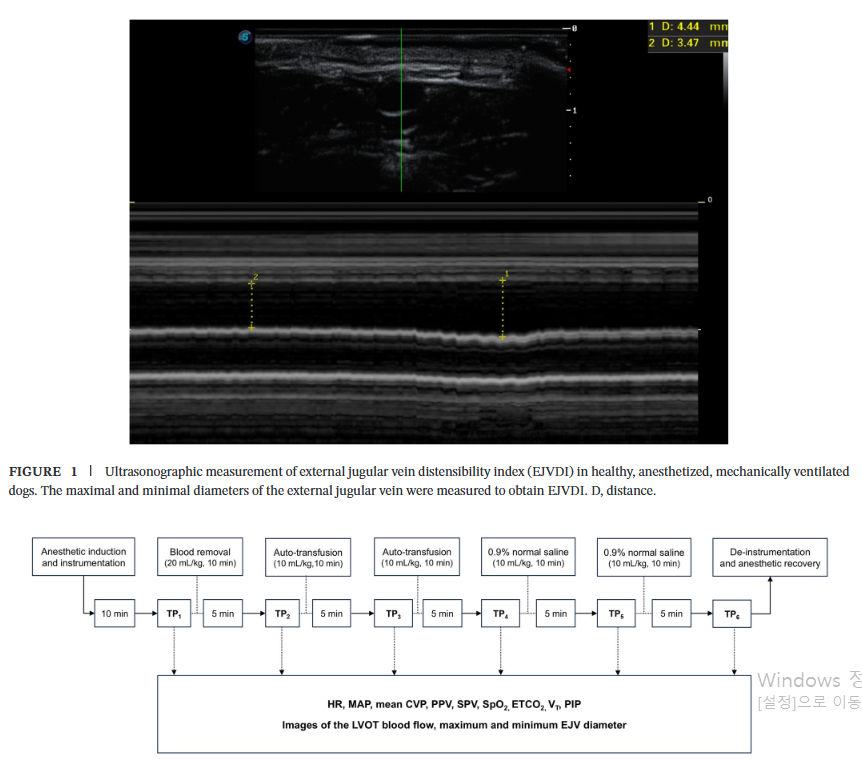

이번 연구는 건강한 비글견 6마리를 대상으로 한 전향적 실험 연구로 진행되었습니다. 모든 개는 마취 후 기관 삽관 및 기계 환기를 적용받았으며, 등쪽으로 누운 자세를 유지했습니다. 연구진은 의도적으로 혈액을 채취하여 혈액량 감소 상태를 유도한 뒤(), 다시 자가 수혈() 및 생리식염수()를 주입하는 방식으로 총 6단계에 걸쳐 혈액량에 변화를 주었습니다.

각 단계에서 연구진은 심박수, 혈압, 중심정맥압(CVP) 등 기본적인 혈역학 지표와 함께, 초음파를 이용하여 좌심실 유출로 혈류 속도(LVOT VTI)와 외경정맥(EJV)의 직경을 측정했습니다. 외경정맥의 직경은 호흡 주기에 따라 가장 커졌을 때(흡기, )와 가장 작아졌을 때(호기, )를 각각 측정하여 다음 공식으로 EJVDI를 계산했습니다.

수액 공급 후 LVOT VTI가 15% 이상 증가한 경우를 '수액 반응군(FR)'으로, 그렇지 않은 경우를 '수액 비반응군(FNR)'으로 정의하여 EJVDI의 예측 능력을 평가했습니다.